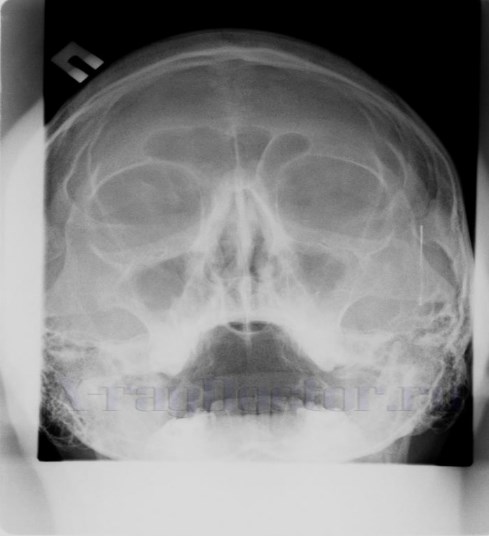

Снимок с хроническим синуситом (двусторонние пристеночные наложения)

Под влиянием медикаментозного лечения отечно-катаральная форма не переходит в хроническое состояние. Когда патология приобретет хроническое течение, на снимке не прослеживаются горизонтальные уровни. При динамической рентгенографии в данном случае не будет специфических изменений.

Серия последовательных рентгенограмм при хроническом гипертрофическом синусите не показывает изменений.